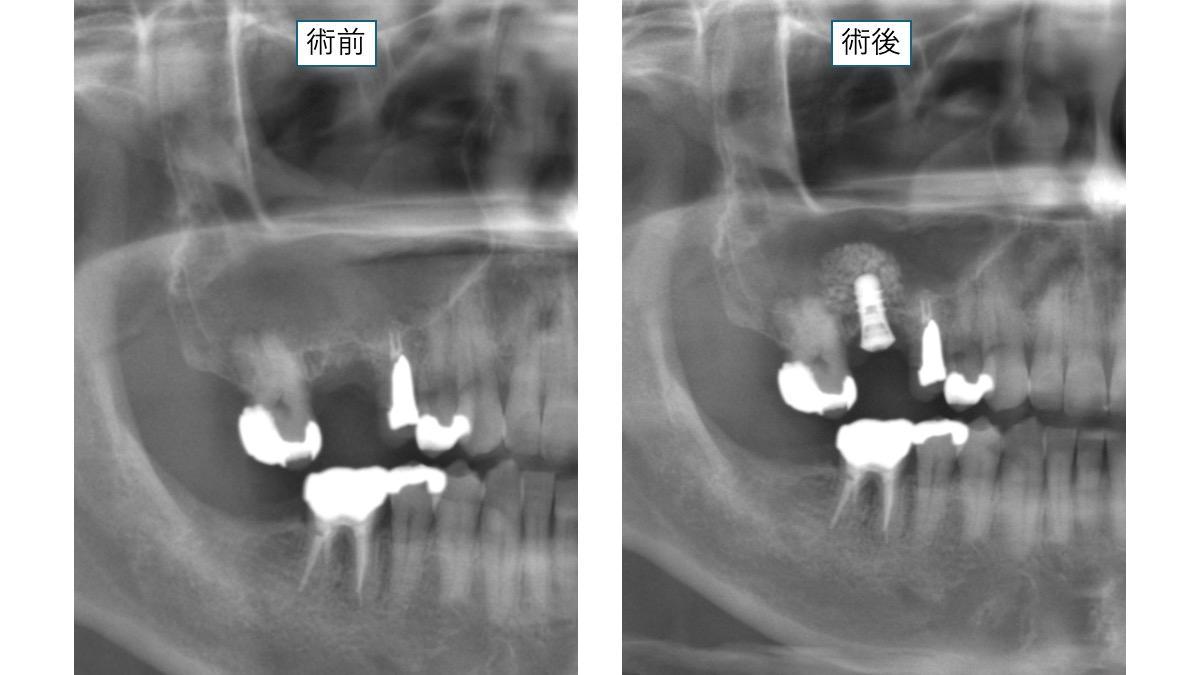

この写真は上の奥歯に骨を足してインプラントをしたケースです。

上の奥歯は骨が少ない人が多いので、このようなサイナスリフトと言われる骨を足す処置が必要となるケース

が多いです。